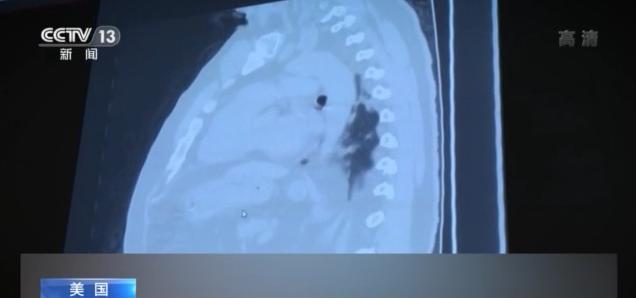

美国新冠肺炎疫情的失控让各地的医院承受着前所未有的巨大压力,医护人员长期处于高负荷工作状态。美国有线电视新闻网的记者日前再次对6月份曾经探访过的医院——休斯敦联合纪念医疗中心——进行了回访,那里的医生和护士坦言,休斯敦乃至得克萨斯州的疫情越来越严重,他们看到了太多的死亡。

今年6月,由于新冠肺炎住院患者太多,得克萨斯州休斯敦联合纪念医疗中心将两个普通病区改造为新冠肺炎隔离病区,而现在,由于患者人数激增,医院不得不再增加一个隔离病区。

根据约翰斯·霍普金斯大学的统计数据,得克萨斯州过去7天新增确诊病例113049例,平均单日新增确诊病例数再创新高,超过16000例,较上一周又增加了15%。